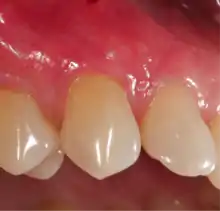

Exposure of the tooth root due to loss of keratinized tissue around the neck of a tooth is referred to as gingival recession. This can result in sensitivity or pain from the exposed tooth root surface (dentin is more permeable and soft compared to enamel and dentin is what makes up the tooth root).[7] Recession may also cause an unasthetic appearance especially if located in the anterior dentition (front teeth). While not all cases of gingival recession require surgical correction, there are various options if that is what the patient desires.[8] It should be reinforced that recession left untreated will not result in tooth loss, contrary to popular belief. Also, recession that is left untreated can be maintained and the inflammation kept at bay with proper brushing and oral hygiene technique.[5] On the other hand, if one desires to pursue corrective therapy, there are a wide variety of techniques ranging from autograft (your own tissue, usually taken from the palate), allograft (someone else's tissue, cadaver), xenograft (animal, usually porcine or bovine) or simply repositioning of the tissue native to the site.[9] The benefits of corrective therapy often result in decreased sensitivity through coverage of the root surface in addition to a gain in the keratinized tissue mentioned beforehand.

Gum grafting, also known as a gingival graft or periodontal plastic surgery, is a surgical procedure to reverse gum recession. Gum recession exposes the roots of teeth,[10] which can lead to sensitivity and put teeth at a higher risk of damage or disease[11] due to the loosening of their attachment within the gums and bones of the jaw. Should gum recession continue, bone and keratinized tissue will be at greater risk of being damaged and permanently lost around the teeth. The aim of a gum graft is to extend keratinized tissue of the gums to cover tooth roots,[12] which restores their firm placement within the jaw and prevents further damage.

Through the advent of micro-surgical procedures these procedures have become more predictable and comfortable for the patients. Gum grafts are usually performed by periodontists who are trained in these procedures, though general-purpose dentists may offer the procedures themselves. Outcome comparisons between both are highly variable, though with periodontists being specially-trained, periodontists generally recommend patients seeking their services over general-practice dentists. A literature review in 2018 showed that the amount of gum recession patients had was reduced after most types of root coverage periodontal surgery procedures. Reported unwanted outcomes were discomfort and pain, mostly related to the site where the tissue graft was taken.[28] This usually occurred in the first week after surgery and had no influence on root coverage outcomes. Currently, more research is needed to determine whether one root coverage technique is more effective than others.[28]